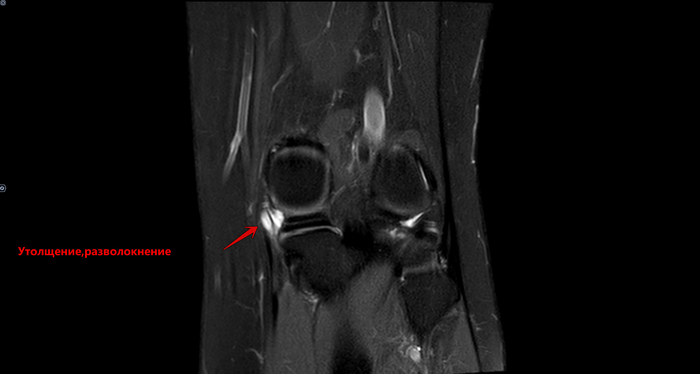

Описание: В структуре внутреннего мениска левого коленного сустава определяется линейный продольный косогоризонтальный патологический МР-сигнал от повреждения с распространением на дистальную суставную поверхность в области тела, заднего рога (соответствует IIIа ст. по Stoller). В области заднего рога медиального мениска определяется многокамерная киста, размерами 1,6х0,7х1,5 см.Целостность крестообразых связок сохранена.В области энтезиса сухожилия медиальной головки икроножной мышцы определяется утолщение, разволокнение.В области сухожилия полуперепончатой мышцы определяется многокамерное жидкостное образование неправильной формы, размерами 1,0х2,8х4,0 см (киста Бейкера).Краевых остеофитов нет.Интенсивность сигнала от клетчатки Гоффа без особенностей. Убедительных данных за патологические изменения остальных видимых мягких тканей не получено.

Заключение:

МР картина повреждения внутреннего мениска (IIIа по Stoller) левого коленного сустава; интерстициальное повреждение внутренней коллатеральной связки; энтезопатии сухожилия медиальной головки икроножной мышцы. Умеренный синовит, супрапателлярный бурсит. Киста заднего рога медиального мениска. Киста Бейкера.